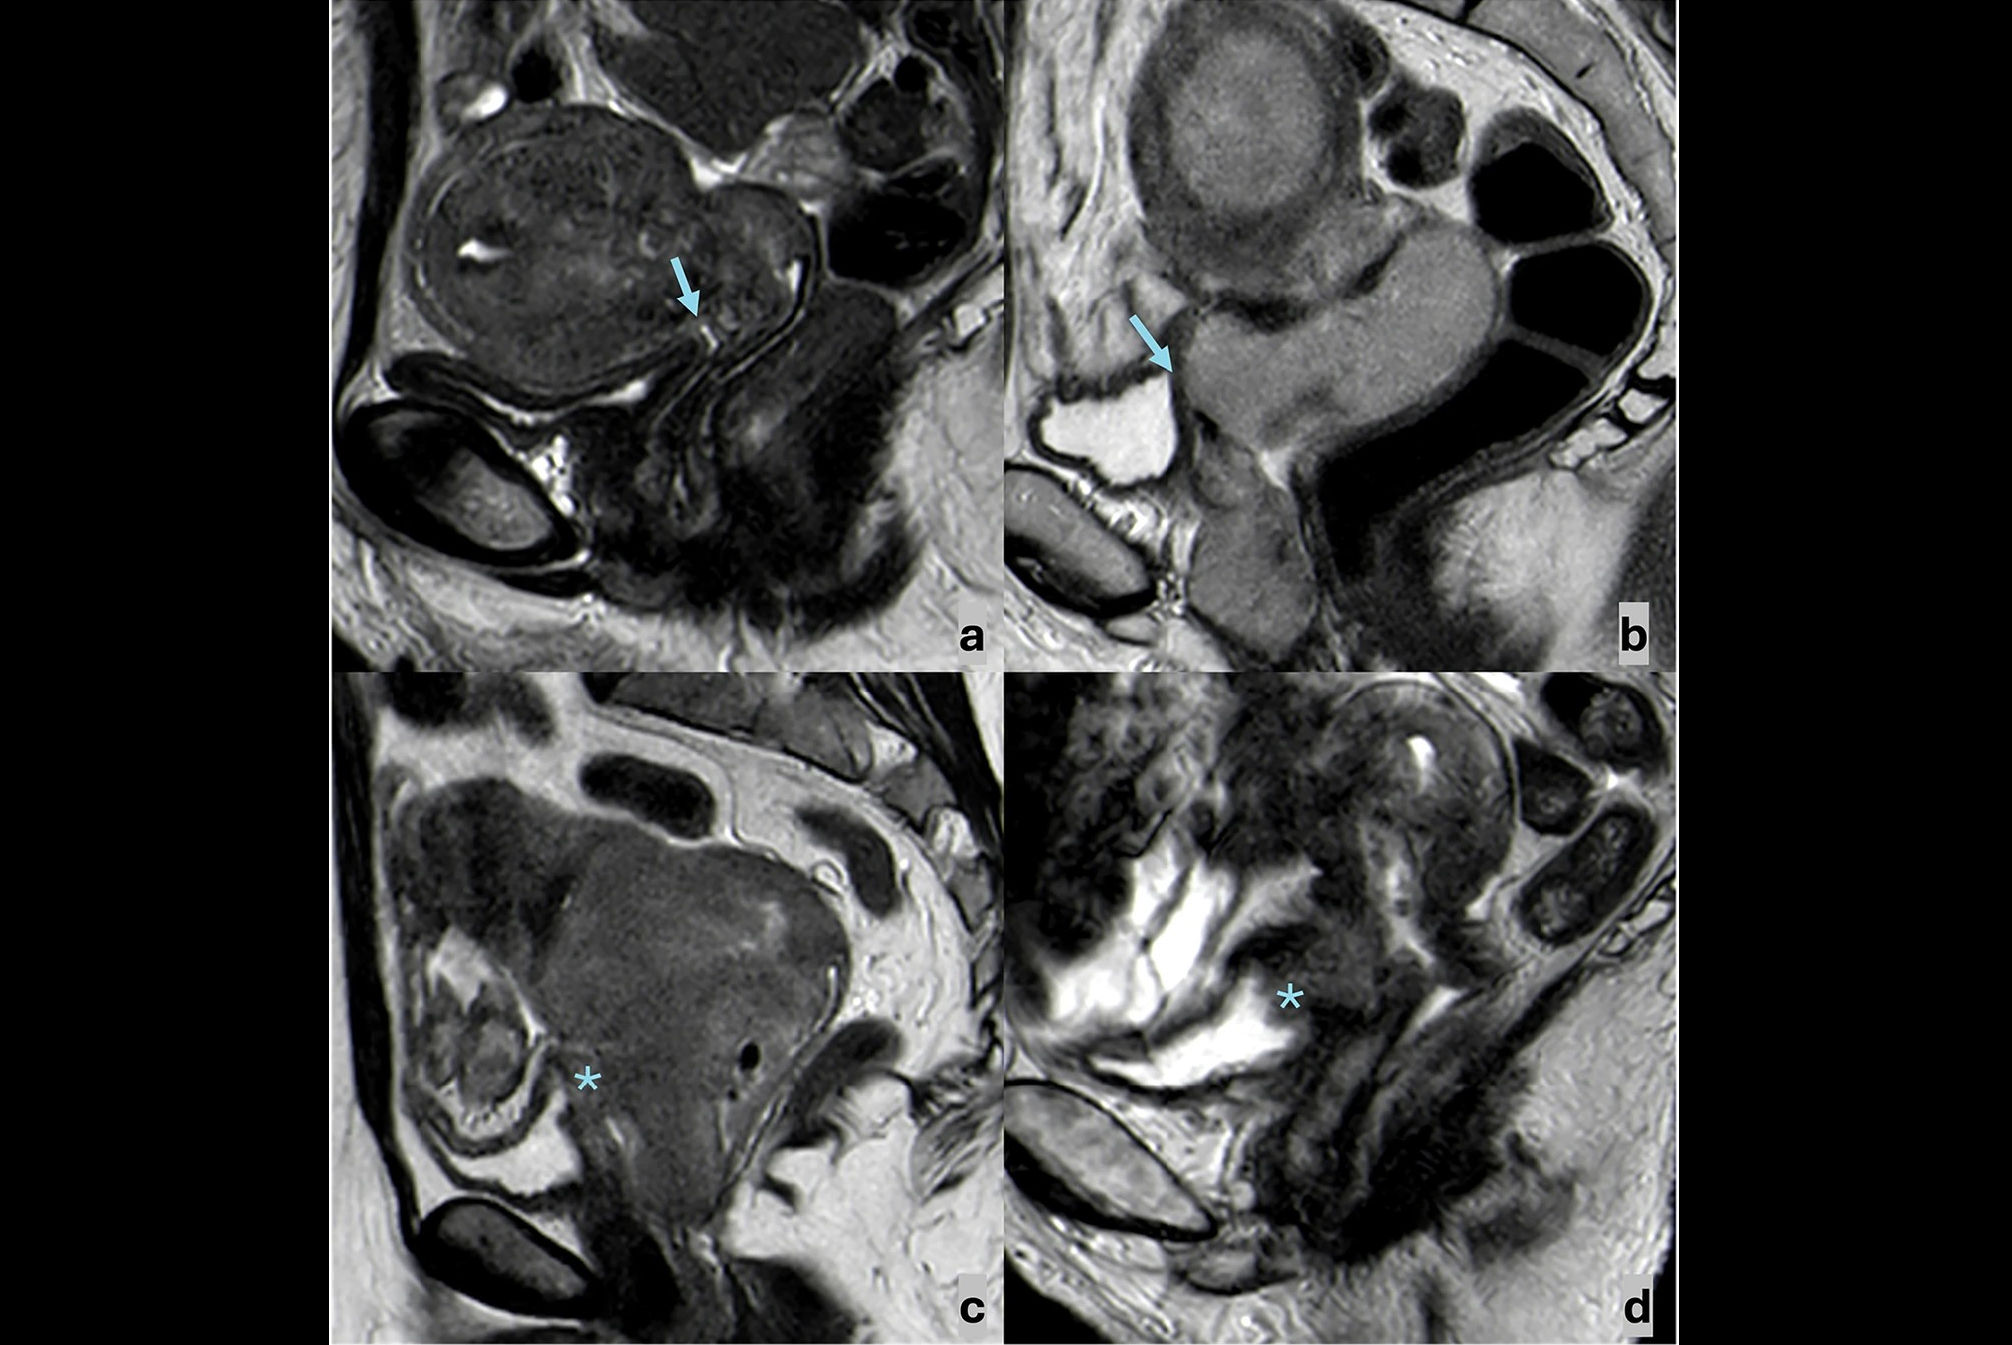

Editor's Note: The image used to introduce this article on our homepage is an MRI scan obtained during straining and evacuation. A large anterior rectocele develops, associated with descent of the posterior pelvic floor. Courtesy of Dr. Francesca Maccioni, Sapienza University of Rome.